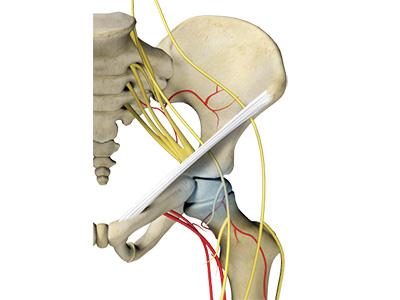

Nerves and Arteries

Nerves of the hip transfer signals from the brain to the muscles to aid in hip movement. They also carry the sensory signals such as touch, pain, and temperature back to the brain.

The main nerves in the hip region include the femoral nerve in the front of the femur and the sciatic nerve at the back. The hip is also supplied by a smaller nerve known as the obturator nerve.

In addition to these nerves, there are blood vessels that supply blood to the lower limbs. The femoral artery, one of the largest arteries in the body, arises deep in the pelvis and can be felt in front of the upper thigh.